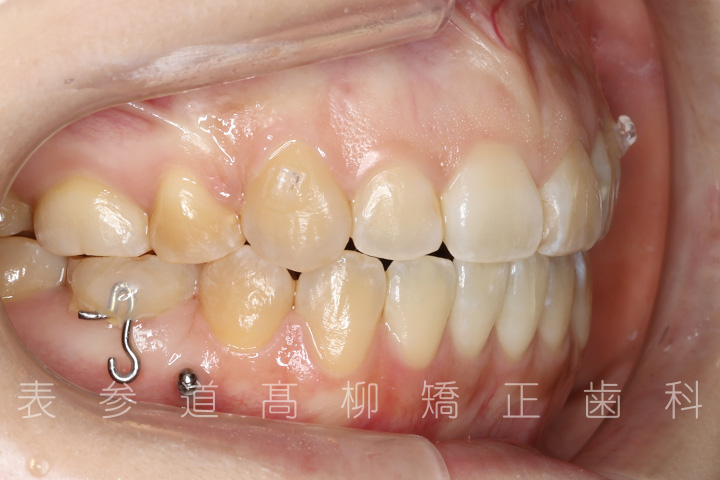

• 6ヶ月後

• 12ヶ月後

• 21ヶ月後

• 25ヶ月後

・金属アレルギーのため、マウスピース型矯正装置を多く設定し、ワイヤーでの矯正治療期間を短縮

・マウスピース型矯正装置と歯科矯正用アンカースクリュー(i-station)を併用し、上顎臼歯部を圧下

・歯科矯正用アンカースクリュー(i-station)を併用し、前歯部を後方へ移動する

・歯科矯正用アンカースクリューを併用し、口下顎大臼歯の近心移動(前方への移動)

・上下歯列の緊密な咬合関係の確立に顎間ゴムを併用(装着時間20時間以上/日)

・マウスピース型矯正装置による嚙み合わせの微調整